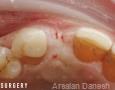

Pictures

Surgery